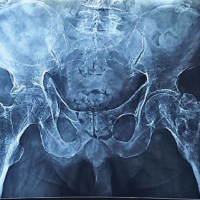

Magnetic resonance imaging (MRI) of the right leg with angiogram showed slow flow vascular malformation involving the subcutaneous and muscle plane of the right leg and foot, with bony hypertrophy of the fibula(Fig. 5).The shape of the talus was abnormal, but there was no subtalar arthritis.

Clinically, the patient presented with swelling and bluish-purple skin discoloration, accompanied by prominent dilated veins on the lateral aspect of the right lower leg and ankle. The radiograph of the left leg revealed fibula hypertrophy. MRI of the right leg, including an angiogram, indicated a slow-flow vascular malformation. The combination of clinical presentation and imaging findings strongly suggested a diagnosis of KTS. The Hamburg classification system (Table 1) is used to categorize vascular anomalies based on their clinical and pathological features. KTS falls under the category of “Combined Vascular Malformations” under the Hamburg classification.

Early involvement of an orthopedic specialist is critical in cases of limb-length discrepancy to determine the best timing for intervention to enhance symmetry by skeletal maturity. Discrepancies of <2 cm are generally managed without surgery. The rate of limb overgrowth in KTS varies, but significant progression of limb-length discrepancy is uncommon after age 12. Due to hypertrophy of the fibula, joint space narrowing can lead to the early onset of arthritis. Regular radiographs are important for monitoring and predicting the appropriate timing for surgical intervention [12].